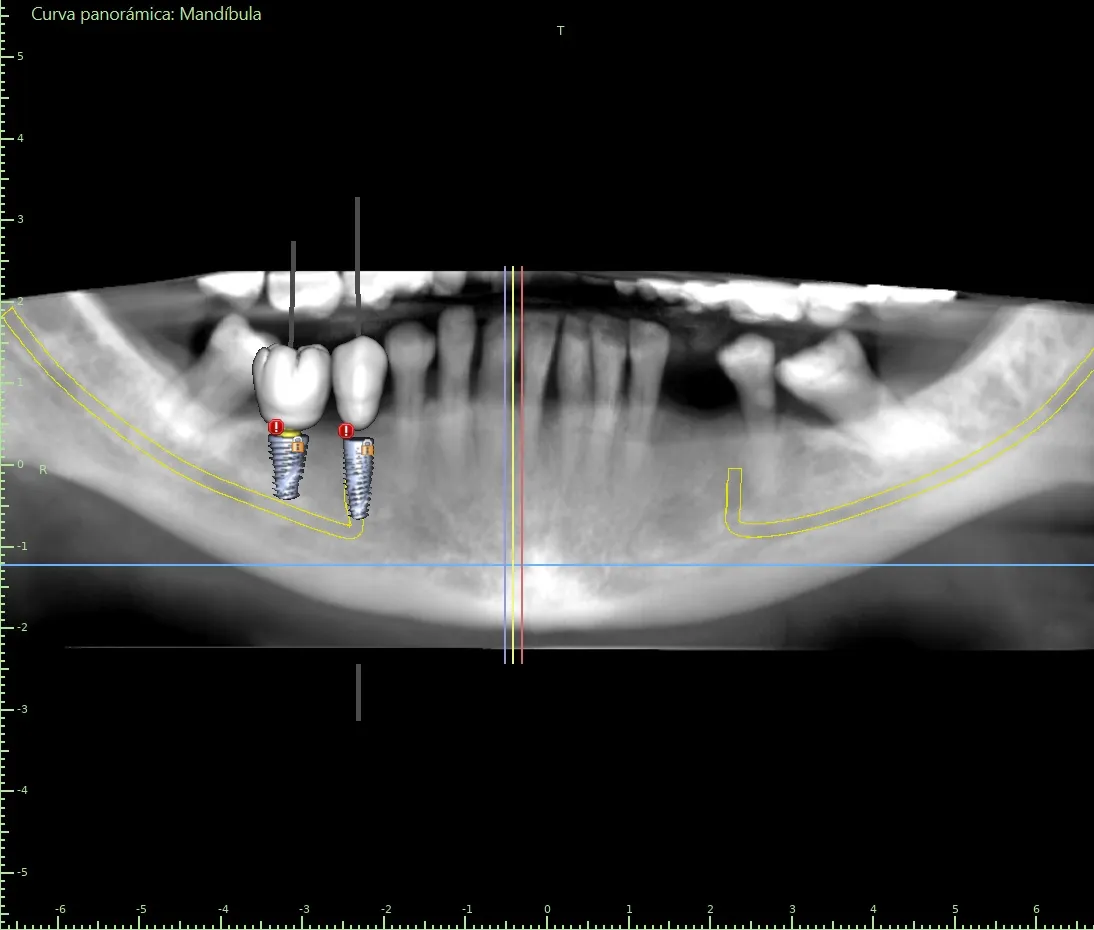

- Safety: It allows for the identification and marking of vital anatomical structures (like the inferior alveolar nerve or the maxillary sinus). The surgical guide ensures the implant is placed at a safe distance from these structures, drastically reducing the risk of complications such as paresthesia (numbness of the lip) or sinusitis.

- Precision: It eliminates the guesswork and variability of freehand surgery. The implant is placed with submillimetric accuracy, exactly where it was planned.

Ideal Prosthetic Results ("Prosthetically-Driven" Approach)

This is a paradigm shift. Traditionally, implants were placed "where there was bone." With guided surgery, the implant is placed in the ideal position for the future tooth (the crown).

- Better Aesthetics and Function: The implant emerges from the gum at the perfect angle and position so that the crown looks natural, functions correctly, and is easy to clean.